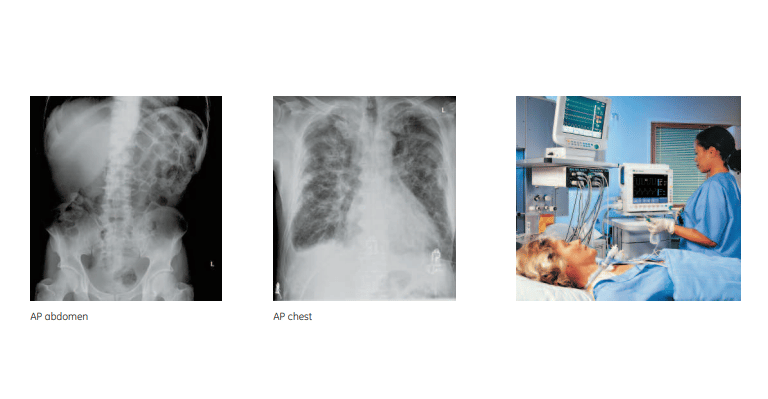

Respiratory and Chest Imaging:

The system is also suitable for imaging lungs and chest cavities in patients suffering from respiratory conditions such as pneumonia, tuberculosis, and chronic obstructive pulmonary disease (COPD). Fast and clear imaging helps healthcare providers make rapid assessments in these cases.